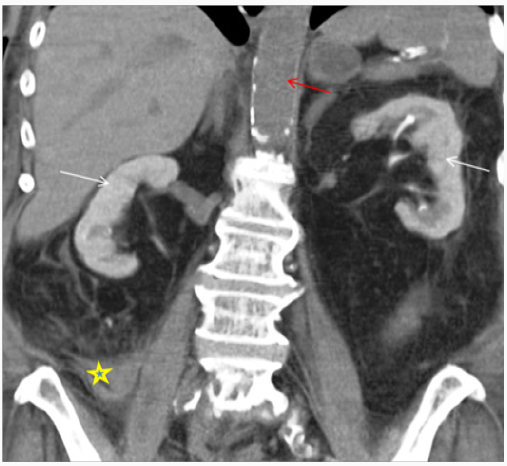

Diagnosing CIN is challenging. It is important to follow systemic approach while evaluating patient with AKI. CIN is a diagnosis of exclusion after other causes of AKI (prerenal/intrinsic/post renal) have been ruled out. There is temporal relationship with contrast exposure, however this should not preclude from searching for other reversible causes of AKI, which may coexist [13-15]. Periprocedural hypotension, bleeding, release of athero-embolic material and use of catheter exchanges may further complicate renal tubular injury after angiography [21]. After exposure to intravascular iodinated contrast, serum creatinine typically rises within the first 24-48 hours, peaks at 3-5 days and returns close to baseline within 1-3 weeks. In most cases, it is asymptomatic and has no significant clinical consequences. However, in rare cases it can lead to oliguria or anuria, irreversible renal damage and need for renal replacement therapy. Basic work up includes clinical assessment, urine output, urinalysis and renal imaging. Volume depleted state can predispose patient to CIN; however CIN can result in intrinsic renal injury with tubular necrosis in extreme cases. Finding on urinalysis may include muddy brown granular cast, tubular epithelial cells and minimal or no proteinuria. Urine examination is neither sensitive nor specific to diagnose CIN, however its usefulness is mainly to exclude underlying glomerular disease or acute interstitial nephritis [22]. Urine studies may show intrinsic renal injury picture with urine sodium < 10 mEq/L, fractional excretion of sodium <1% and urine osmolality <350 mOsm/kg. Persistent nephrogram (Figure 1) may be incidentally seen on follow up imaging because of delayed clearance of contrast [23].

There has been number of preventive measures to reduce incidence of CIN in high- risk population, however there is no clear consensus and current evidence remains inconclusive [64,65]. However, it has been agreed that identification of highrisk population is the foremost. Once this population is identified, best attempt should be done to minimize renal injury by stopping other nephrotoxic medications particularly NSAIDS, loop diuretics and met formin at least 24-48hours prior to contrast exposure particularly if IA exposure is anticipated and in patients with baseline severe insufficiency [47,57,58]. Unfortunately, in emergent procedures it might not be possible to stop medications or delay the procedure, however when possible restarting the nephrotoxic medication should be delayed for at least 48 hours after or as deemed clinically appropriate (Figure 1).

Figure 1: 68-year-old female with drop in hemoglobin status-post cardiac catheterization one day ago. Non-Contrast enhanced CT Abdomen demonstrating persistent nephrogram phase of enhancement from prior cardiac catheterization due to contrast induced nephropathy. Note hyperdense collection suggestive of an acute hematoma extending adjacent to RIGHT psoas muscle (*) lateral to the RIGHT psoas muscle continues with RIGHT iliac vessels, likely cause of drop in hemoglobin. Red arrow depicting no intra-vascular contrast media in the current study.